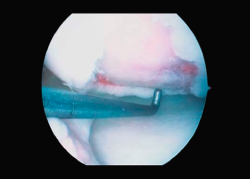

First surgery involves arthroscopy of the damaged joint. It assesses the chondral lesion to be treated and confirms whether it is amenable to the chondrocyte implantation technique (Figures 1 and 2). Other procedures are also carried out if needed, such as for example reconstruction of the anterior cruciate ligament, partial meniscectomies, meniscus implantation, patellar realignments, osteotomies, etc. Lastly, the cartilage sample is taken from a non-weight bearing zone (intercondylar zone or internal femoral condyle at its upper margin). The sample is extracted with biopsy forceps or, alternatively, using discectomy forceps. Between 3-4 rice grain-sized fragments of healthy cartilage are harvested (Figure 3). The biopsy material is placed in a sterile receptacle containing a culture medium (DMEN) (Figure 4). The material is kept at room temperature and is shipped to the laboratory as quickly as possible. A form should be completed (Figure 5), stating the joint, the location of the lesion and the size of the defect. Once in the laboratory, the sample is processed and cultured. After 4-6 weeks (depending on the case), the culture is ready for implantation.

Figure 2. Arthroscopic view of an Outerbridge grade IV chronic chondral lesion of the internal femoral condyle.